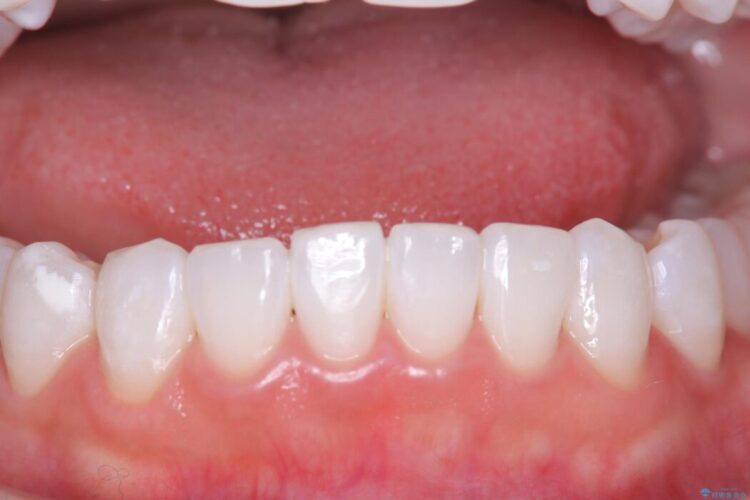

長期的な安定性を重視したセラミック治療

歯と歯の間に虫歯があった患者様です。

治療期間(治療回数):1ヶ月(2~5回) | 概算治療費:13.2万円(税込)(仮歯:10,000円+オールセラミッククラウン 3年保証110,000円)